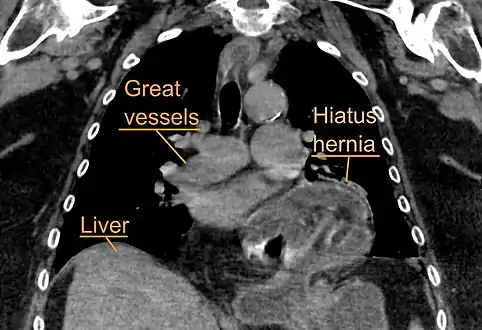

Diagnosis

The diagnosis of a hiatal hernia is typically made through an upper GI series, endoscopy, high resolution manometry, esophageal pH monitoring, and computed tomography (CT). Barium swallow as in upper GI series allows the size, location, stricture, stenosis of oesophagus to be seen. It can also evaluate the oesophageal movements. Endoscopy can analyse the esophageal internal surface for erosions, ulcers, and tumours.

Meanwhile, manometry can determine the integrity of esophageal movements, and the presence of esophageal achalasia. pH testings allows the quantitative analysis of acid reflux episodes. CT scan is useful in diagnosing complications of hiatal hernia such as gastric volvulus, perforation, pneumoperitoneum, and pneumomediastinum.[8]